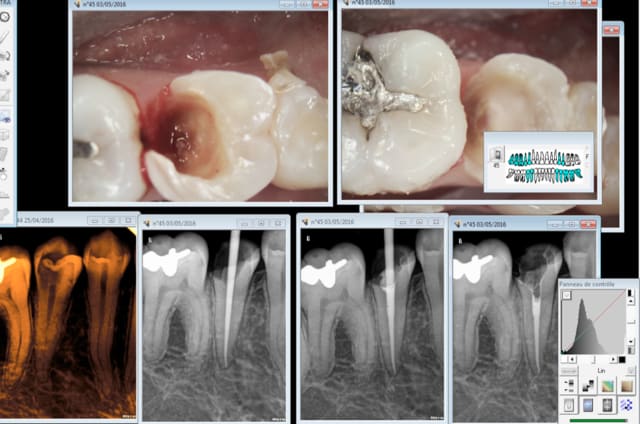

Rentrons dans le vif du sujet Ces 2 cas justifient ils de recourir à un inlay core ?

J ai vu des cas comme ceux là gères en endocouronne à recouvrement très partiel hormis la partie proximité, sans objection de ma part. (no post je precise)

Je n en verrai pas plus pour une option thérapeutique inlay core couronne.

Cas concret la rétro coronaire de cette 35 nous montre une grosse lésion carieuse. Je fais donc une rétro alvéolaire pour voir si il n'y a rien à l'apex et qui me servira de radio pré op dans le cas probable d'une endo. je ne vais pas irradier le patient inutilement pour avoir la totalité de la 46 et éviter un indu potentiel . Non ? -)